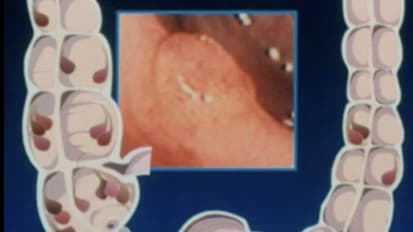

Colon (including Inflammatory Bowel Disease), TPN/Nutrition